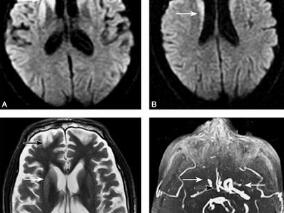

1小时条评论侧窦血栓临床较少见,发病率低,临床表现复杂多样,缺乏特异性,容易误诊和漏诊而影响预后。现将本病例分析如下。 1 病例简介 患者男,21岁,学生,因头痛、呕吐、发热半月余,精神异常3日,于2008年11月10日入我院治疗。患者半月前有上呼吸道感染史,之后一直伴...